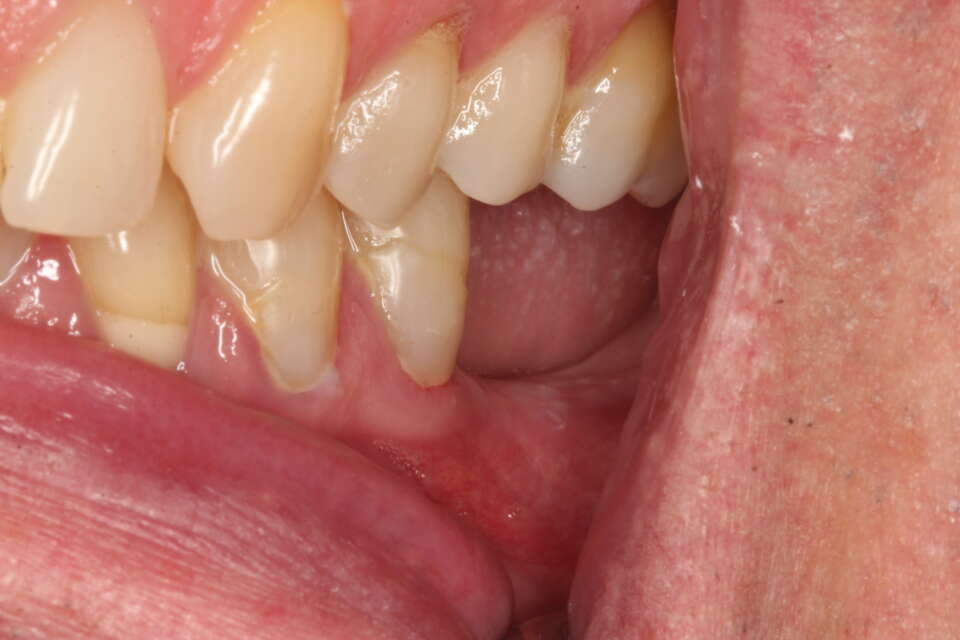

IMG 7535

Missing molars on the left side